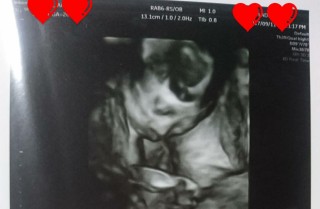

大きめの1450gで先生にびっくりされました(笑) 臍の緒を枕にしている様でした☆